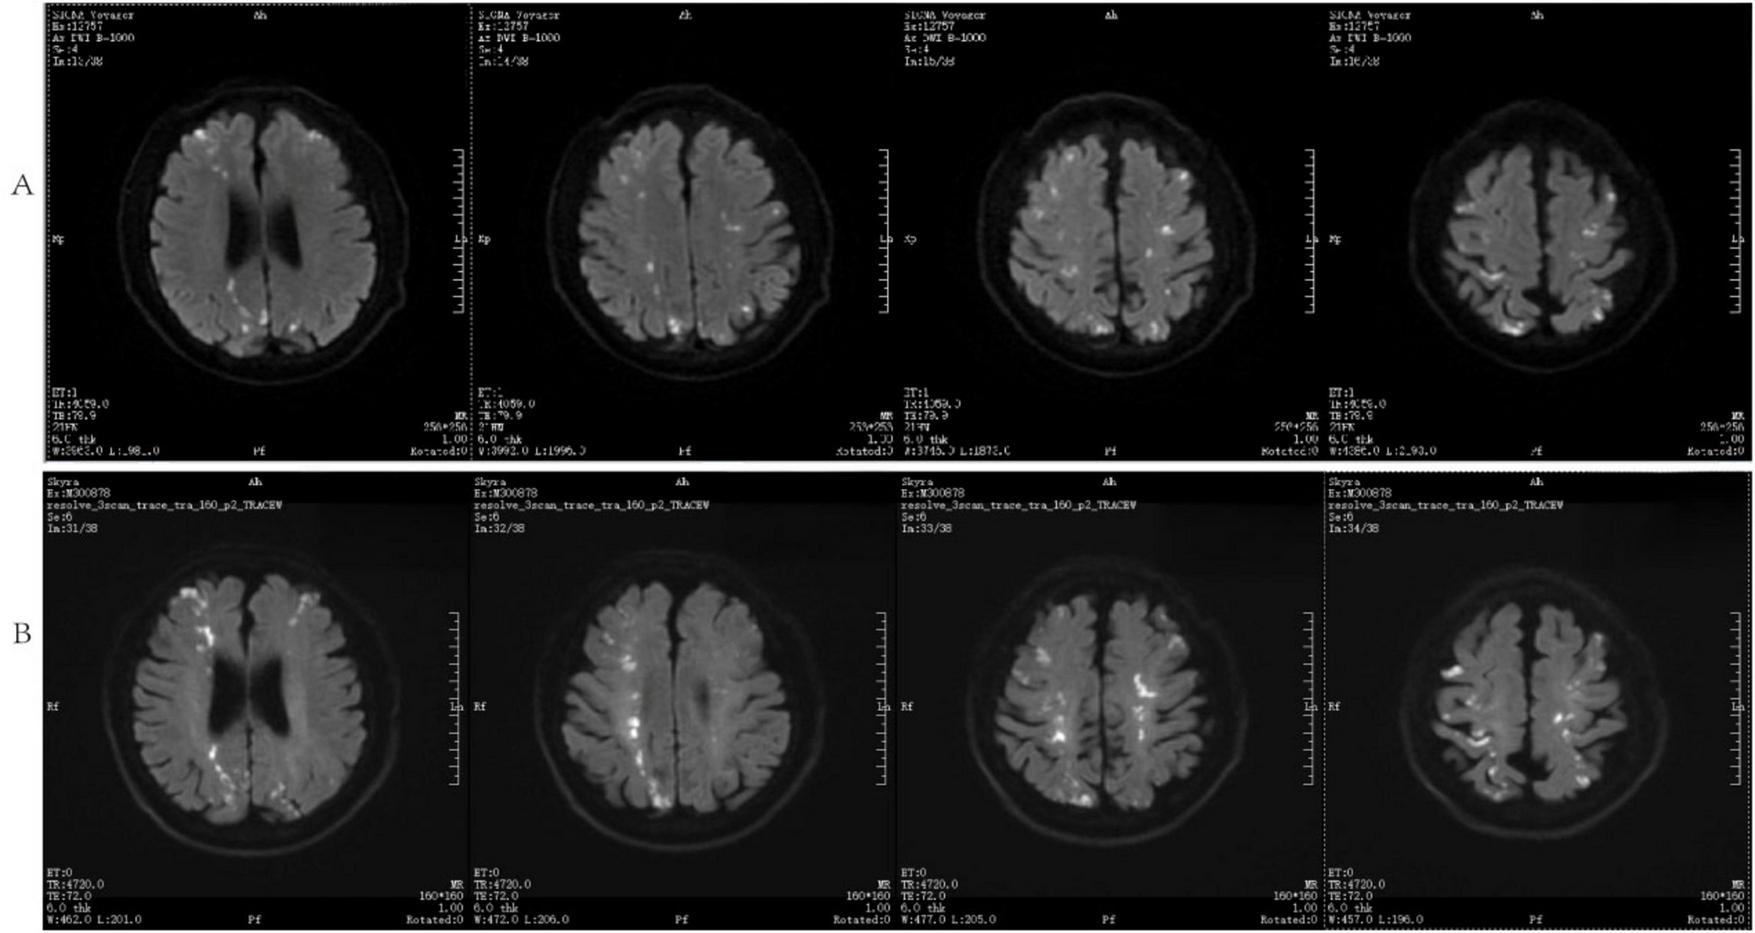

The patient was admitted to the hospital, and a cranial vascular CTA examination revealed cerebral atherosclerosis without obvious vessel stenosis (see Figure 1); a cranial MRI and DWI examination revealed bilateral cerebellar, bilateral frontal-parietal-temporo-occipital, and semiovoid central region infarcts (see Figure 2A); troponin levels were 0.224 ng/ml [ref (ref), 0.0–0.08 ng/ml], Creatine kinase isoenzyme 34 U/L [ref, 0.0–24 U/L], N-terminal brain natriuretic peptide precursor (BNP) 1324 pg/ml [ref, 0.0–300 pg/ml], and an electrocardiogram that suggested an ST-segment abnormality. Cardiovascular consultation was sought to rule out a non-ST-segment elevation myocardial infarction, and antiplatelet aggregation and lipid-modulating therapy were administered. The percentage of eosinophils was 43.4% [ref, 0.4%–8%], and tests for coagulation function, lipids, and liver and renal function revealed no appreciable abnormalities. Two days later, the patient developed severe precordial discomfort and dyspnea. Concurrently, limb muscle strength decreased significantly. On March 31, a physical examination revealed grade 3 muscle strength in the left upper limb, 0 in the right upper limb, and grade 2 muscle strength in both bottom limbs. Figure 3 depicts muscle strength scores provided by the Medical Research Council (MRC). Troponin, creatine kinase isoenzyme, and eosinophil percentage were all steadily declining compared to the prior time frame. As shown in Figure 3, the acidophilic fraction increased steadily. He was moved to the critical care unit (ICU) on March 31 in order to receive correctional treatment. According to a perfect coronary CTA examination, the coronary artery wall had many segmental mixed plaque formation, mild stenosis in the lumen, and an anterior descending branch of the middle section of the stent, which was about 2.3 cm long. The stent did not exhibit any visible fractures or restenosis symptoms, as shown in Figure 4. Bilateral cerebellum, bilateral frontal-parietal-temporo-occipital and semiovarian central area of several spots, and a tiny patchy DWI high signal, measuring between 2 and 18 mm (slightly larger in extent than the previous MR 2025.03.27), were all suggested by the review of the cranial MRI test (see Figure 2B). On April 1, tests revealed a considerably higher eosinophil level. Eosinophilia was discovered following a consultation with the hematology department. To decrease eosinophils, methylprednisolone sodium succinate was administered first, followed by clopidogrel to limit platelet aggregation and low molecular weight heparin for anticoagulation. A bone marrow aspiration was performed to assess flow cytometry, FISH, and fusion genes. Figure 5A shows the flow cytometry results for April 5: an elevated eosinophil percentage. According to the bone marrow aspiration report, there were more eosinophils in the bone marrow and peripheral blood images. Figure 5B shows an increase in eosinophils. Fusion gene screening revealed no results for PCM1:JAK2, ETV6:JAK2, FLT3, ETV6:ABL1, and BCR:JAK2. FISH probe analysis: FGFR1, PDGFRA, and PDGFRB: negative. Low molecular heparin anticoagulation, clopidogrel antiplatelet aggregation, and eosinophils were all reduced by methylprednisolone sodium succinate. Eosinophil counts in the patient progressively returned to normal. The patient’s limb muscle strength improved between 4 and 11; both upper and lower limb muscular strength were grade 3 and grade 4, respectively. He was sent to the rehabilitation department for therapy, and on April 28, he was released from the hospital on June 1. The outpatient follow-up assessment showed that the patient’s limb muscle strength had restored to normal.

FIGURE 2

DWI and cranial MRI (A) inspected on March 27, 2025, (B) analyzed on April 1, 2025.